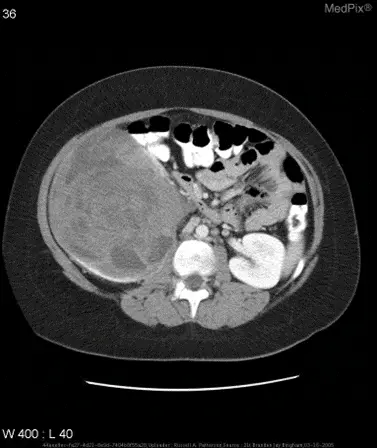

示例及效果

- 場景:某醫院的電子病歷系統中,包含胸部X光圖像,以及報告正文文本。

- 圖像內容:胸部X光圖

- 場景:醫學圖像領域,基於多模態模型實現簡單的診斷。甚至就不需要額外上下文信息。

圖文問答:“大腦的區域是否梗塞?”。

❌ 普通通用模型:無法做出診斷。

✅ 微調後的模型:是的。大腦的區域存在梗塞。

數據簡介

VQA-RAD 是一個關於放射影像的問題-答案對數據集。

- 數據集用途

訓練和測試醫學影像VQA(視覺問答)系統

支持開放式問題(如“病灶位置?”)和二元問題(如“是否存在腫瘤?”)

- 數據來源

基於MedPix(開放醫學影像數據庫)

由臨牀醫生手動標註,確保專業性

- 核心優勢

首個專注放射影像的VQA數據集

結構清晰,覆蓋臨牀常見問題類型

在共451題的測試集中,模型Qwen2.5-VL-3B-Instruct微調前後的精確匹配率和語義相似度如下所示:

- 示例

針對如下影像,微調前後的輸出

- 微調前:

{

"query": "is the liver visible in the image?",

"true": "no",

"infer": "yes, the liver is visible in the image. it appears as a large, dark gray structure located in the upper left quadrant of the abdomen.",

"exact_score": 0,

"cosine_score": 0.3227266048281184

}- 微調後:

{

"query": "is the liver visible in the image?",

"true": "no",

"infer": "no",

"exact_score": 1,

"cosine_score": 1.0

}拓展:ColPali 中的多模態 RAG